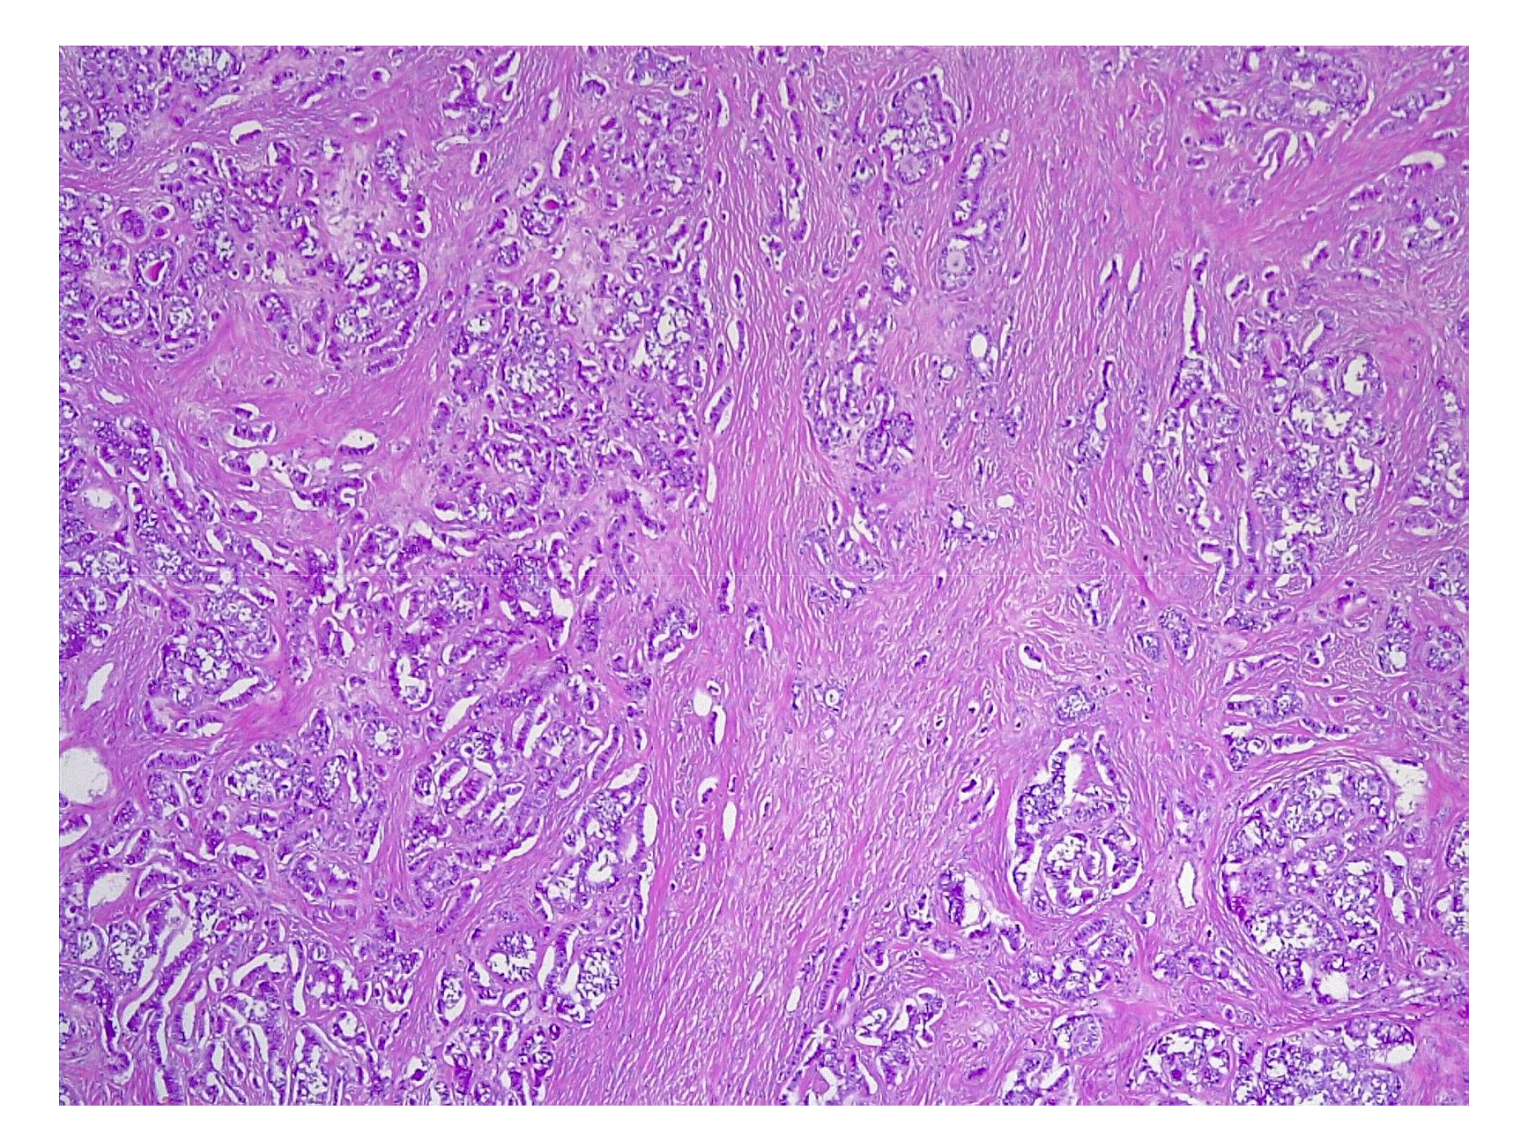

4.2. Histopathology Features